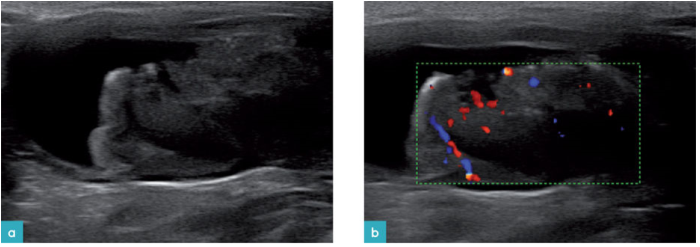

猫的膀胱肿瘤并不常见。移行上皮癌(图13和14)是最常见的肿瘤并呈侵袭性发展,多发于膀胱三角区。也会侵入到尿道里,造成尿道阻塞。

猫膀胱淋巴瘤的表现是多种多样的。一种情况是膀胱壁上长有无柄的分界不清的低回声均质团块。它的血流信号很弱,大多存在于团块的外周。淋巴瘤会波及到膀胱三角区,会造成输尿管阻塞,也可能散布到尿道中。

肿物会波及到膀胱三角区的粘膜层,如果浆膜层变得不规则则说明肿物已经侵袭到了浆膜层。淋巴瘤会造成膀胱壁的广泛性增厚,丢失正常的分层结构。